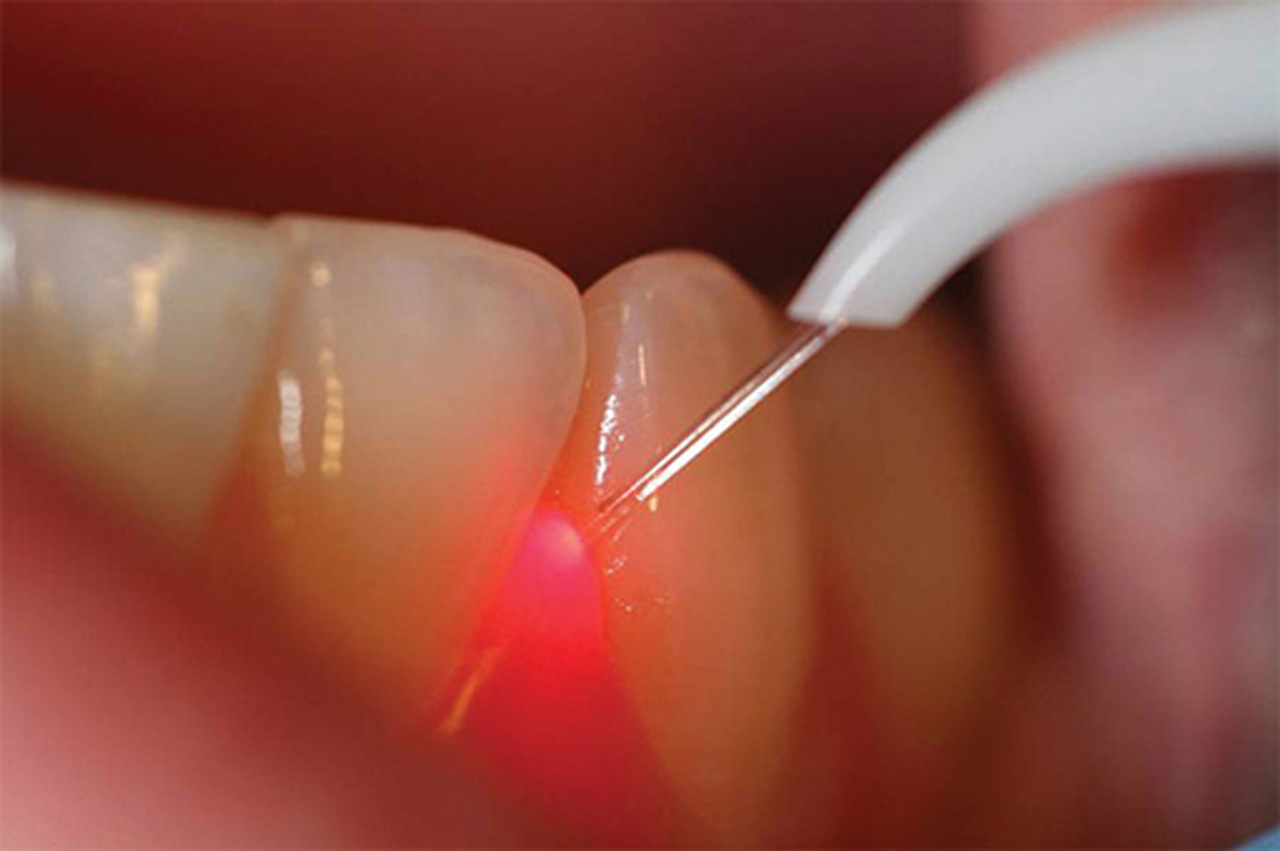

SCALING AND POLISHING